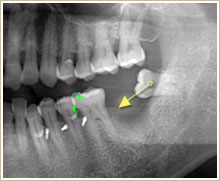

傾斜している親不知を矢印の部位に移動させます。